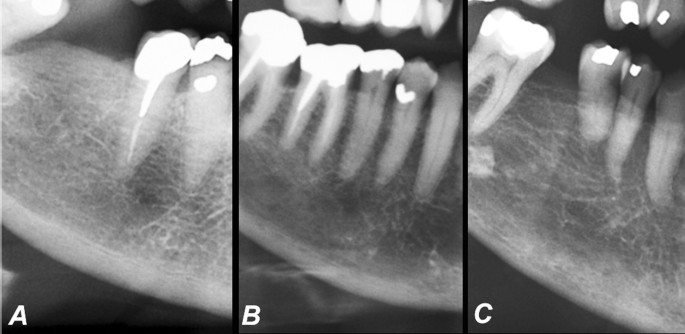

Medidas de Índice Cortical Mandibular realizado bilateralmente cerca... | Download Scientific Diagram